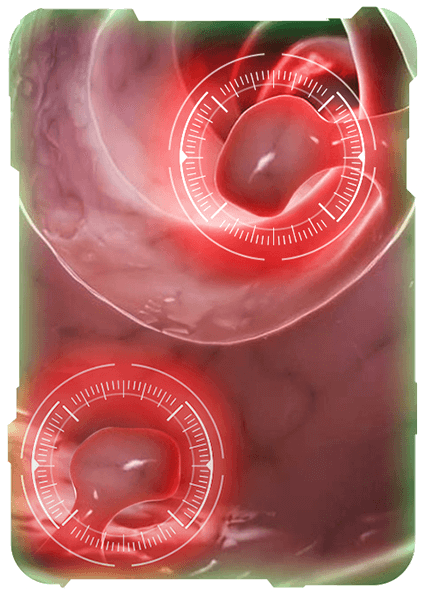

Mục tiêu tầm soát bệnh chính xác để trị hết bệnh, đem lại hạnh phúc cho người bệnh, Phòng khám đầu tư hệ thống máy móc tân tiến hiện nay, giúp bác sĩ đánh giá chính xác tổn thương và giúp sinh thiết chính xác vị trí tổn thương.

Với hệ thống máy nội soi hiện đại cùng công nghệ chẩn đoán hình ảnh tiên tiến, chúng tôi tập trung phát triển dịch vụ nội soi chuyên sâu nhằm phát hiện sớm và chính xác các bệnh lý tiêu hóa.